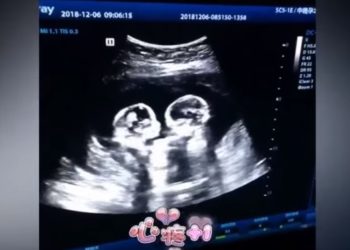

El video de una ecografía realizada en Yinchuan (Ningxia, China) en la que se ve a dos hermanas gemelas "peleándose"...